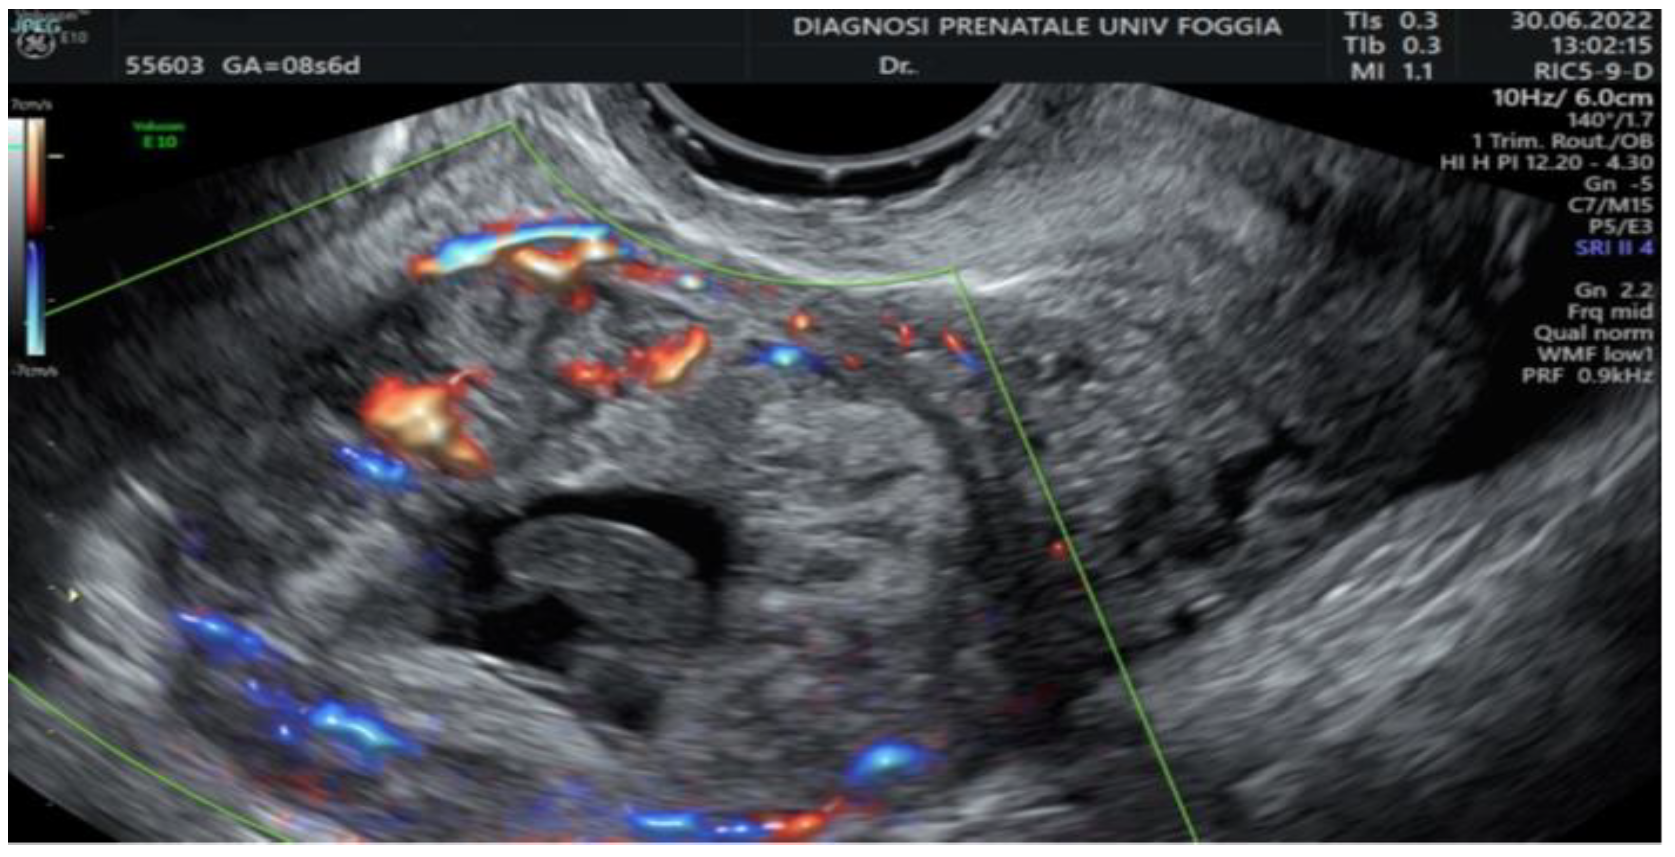

2. Case Presentation